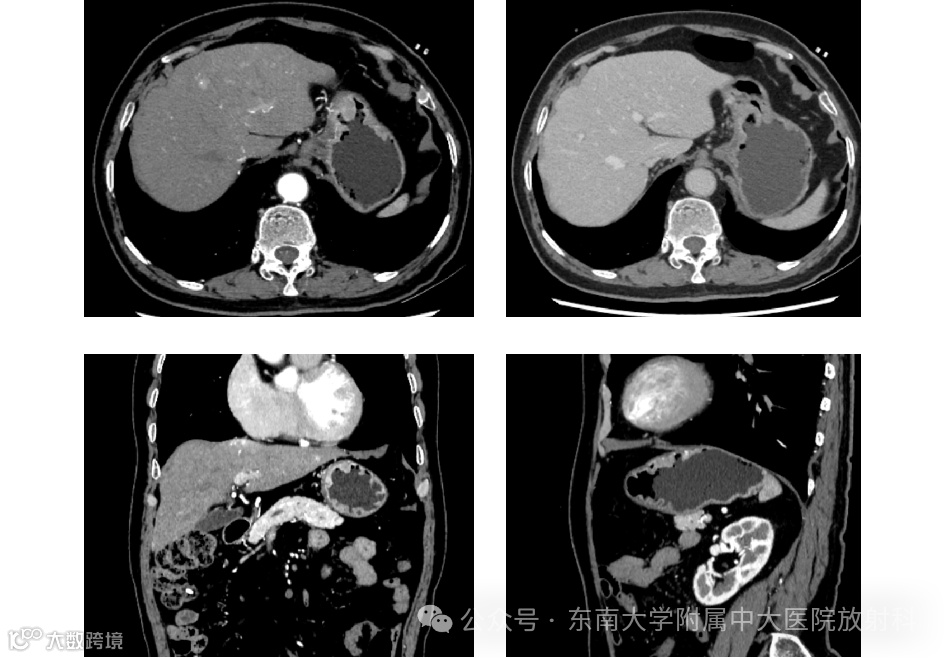

影像学检查